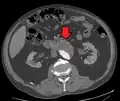

Abdominal aortic aneurysm

three white arrows pointing to an enlargement of the abdominal aorta

CT reconstruction image of an abdominal aortic aneurysm (white arrows)